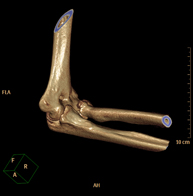

- TC Codo

Exploración radiológica que mediante un sistema de rayos X y detectores que giran alrededor del paciente, reconstruyendo las imágenes por ordenador (TC Multidetector), permite el estudio de huesos, músculos y articulaciones del codo.